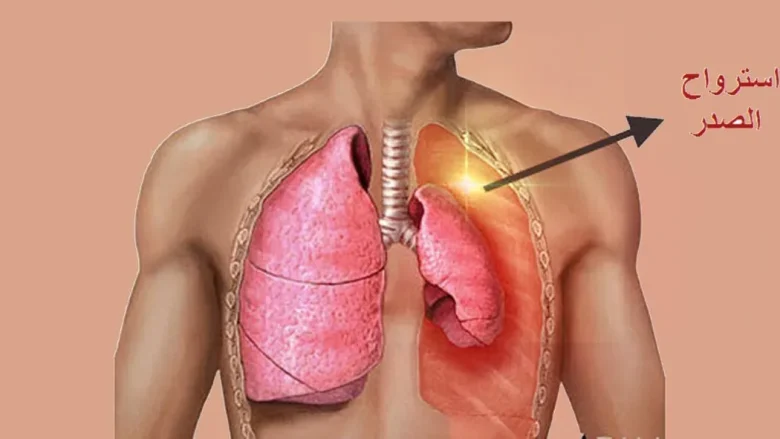

ما هو إسترواح الصدر؟

إسترواح الصدر (Pneumothorax) هو حالة طبية تحدث عندما يتجمع الهواء في الفراغ بين الرئة وجدار الصدر. هذا التجمع يسبب ضغطاً على الرئة مما يؤدي إلى انكماشها أو انهيارها الجزئي أو الكامل. يمكن أن تحدث هذه الحالة بشكل مفاجئ وتعتبر حالة طبية طارئة تتطلب العلاج الفوري.